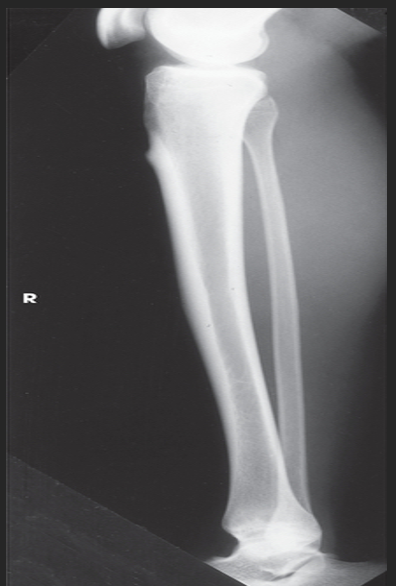

Name this projection.

AP leg (tib fib)

What SID is used?

48 inches

What anatomy is placed parallel to the IR?

Patella and femoral condyles

What position is the patient in?

Supine w/ foot dorsiflexed

What anatomy must be included on the radiograph?

Entire tibia and fibula plus adjacent joints

What should be done if the entire tib/fib cannot fit on the IR?

Either rotate the IR to be diagonal to the leg OR take two separate images (a bigger image of whichever joint is more in pain and a smaller image of the other joint)

How far beyond the adjacent joints should you see light?

1.5"

What part of the tib/fib should be free of superimposition?

Fibula midshaft